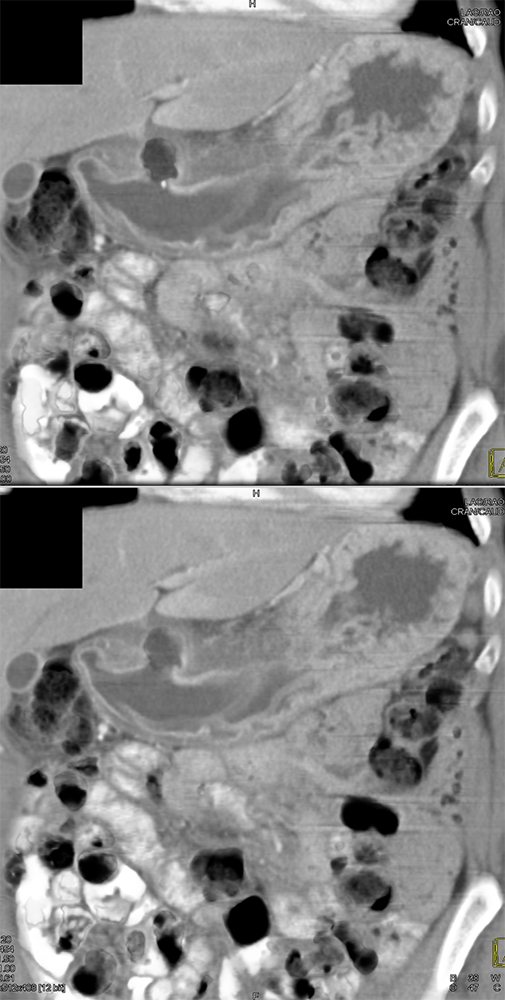

“Gastritis can be secondary to many etiologies including infection, systemic illness such as trauma or burns, and autoimmune disease. Peptic ulcer disease is most commonly caused by Helicobacter Pylori infection and chronic NSAID use . The most common sites for ulcer formation are the gastric antrum/pylorus and proximal duodenum. The resultant edema and fibrosis around the ulcer site can cause narrowing and eventual obstruction of the gastric outlet [9]. Prior to the widespread use of H2 blockers and proton pump inhibitors, peptic ulcer disease was the most common cause of gastric outlet obstruction, however in the era of H2 blockers, outlet obstruction now predicts malignancy. While endoscopy is the modality of choice for diagnosing gastritis, CT is often performed first particularly in the setting of acute abdominal pain.” Imaging of acute gastric emergencies: a case-based review Jetty S et al. Clinical Imaging 72 (2021) 97–113 |

“On imaging, it can be difficult to distinguish benign peptic ulcer disease from malignant causes of gastric outlet obstruction and biopsy is required for confirmation. Peptic ulcers can perforate and should be recognized on imaging.” Imaging of acute gastric emergencies: a case-based review Jetty S et al. Clinical Imaging 72 (2021) 97–113 |

“On CT, gastritis will appear as wall thickening with alternating hyper- and hypoattenuation representing mucosal enhancement and submucosal edema. The presence of mucosal enhancement (hyperemia) on CT suggests gastritis as the cause of gastric wall thickening. An uncommon form of gastritis is emphysematous gastritis. It is usually caused by gas-forming Escherichia coli. Initially obtained AXR may show mottled gas outlining the gastric wall. CT can confirm the diagnosis. Mottled gas can also be a sign of gastric pneumatosis from ischemia.” Imaging of acute gastric emergencies: a case-based review Jetty S et al. Clinical Imaging 72 (2021) 97–113 |

”Primary gastric cancer (GC) is a common cause of cancer related death worldwide and can initially present as a gastric ulcer. The characteristic CT finding in GC is disruption of the multilayered pattern of the gastric wall enhancement with thickening, variable enhancement and ulceration. Malignancy is the most common cause of gastric outlet obstruction. Malignant obstruction is an advanced disease presentation that occurs in up to 20% of patients with primary pancreatic, gastric, or duodenal carcinomas. It can be intrinsic or extrinsic. Extrinsic obstruction is almost always due to compression of the gastric outlet from tumor growth in surrounding organs. It is most commonly seen with primary tumors of the pancreas and duodenum.” Imaging of acute gastric emergencies: a case-based review Jetty S et al. Clinical Imaging 72 (2021) 97–113 |